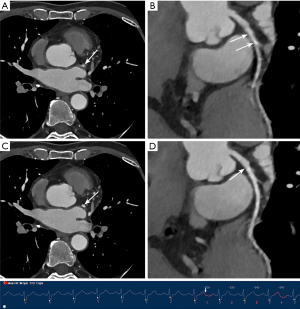

Similarly, the use of MCR significantly improved subjective image quality and interpretability in both subgroups, with a more evident difference observed in the high HR and/or arrythmias group. In the low HR group, although subjective image quality scores performed with MCR displayed a consistent superiority, no significant difference was noted in terms of interpretability by every coronary artery (all P>0.05). Conversely, in the high HR and/or arrythmias group, the application of MCR resulted in a remarkable improvement in interpretability at all levels. Concerning the major three coronary arteries, the greatest benefit in interpretability improvement was found for RCA, where the proportion of arteries considered non-interpretable decreased dramatically from 70.3% to 8.1% (P<0.001). Figures 3-6 display four representative clinical cases, among which Figure 6 contains invasive coronary angiography image.

MCR showed remarkable improvements in subjective image quality and interpretability in the overall population and both subgroups, an observation that was particularly evident for the higher HRs (HR ≥75 bpm), which is consistent with previous research (15,16). Notably, the inclusion criteria of patients with arrhythmia were less strictly controlled in the present study, rendering our study population relatively more representative for an actual clinical scenario. Motion artifacts produced by a constantly beating heart deteriorates the delineation of coronary arteries, especially for patients with AF characterized by high HR and high HR variability, which have traditionally been excluded from CCTA examinations (32,33). However, CCTA with the application of MCR achieved sufficient image quality, tremendously reducing the ratio of segments deemed non-interpretable from 30.0% to 1.9% in the high HR and/or arrythmias group.

Analysis by segments revealed that the mid-segment of the RCA yielded the lowest image quality because it is perpendicular to the scanning plane leading to the most severe motion artifacts (34). As a result, the greatest benefit from MCR was obtained in this segment. In the low HR group, despite the continuous superiority of subjective image quality scores with the use of MCR across all evaluated segments, there was no significant difference regarding interpretability for every coronary artery. A plausible explanation for this result is that patients with lower HRs are less susceptible to motion artifacts due to possessing having relatively longer diastolic phase of the cardiac cycle, usually referred to as the “cardiac quiescence” phase (35). Consequently, there would be less room for the motion-correction algorithm to enhance image quality. Additionally, the sample size of this subgroup was limited, which might be an important factor contributing to the lack of statistical significance. Therefore, MCR showed limited improvements in this regard.